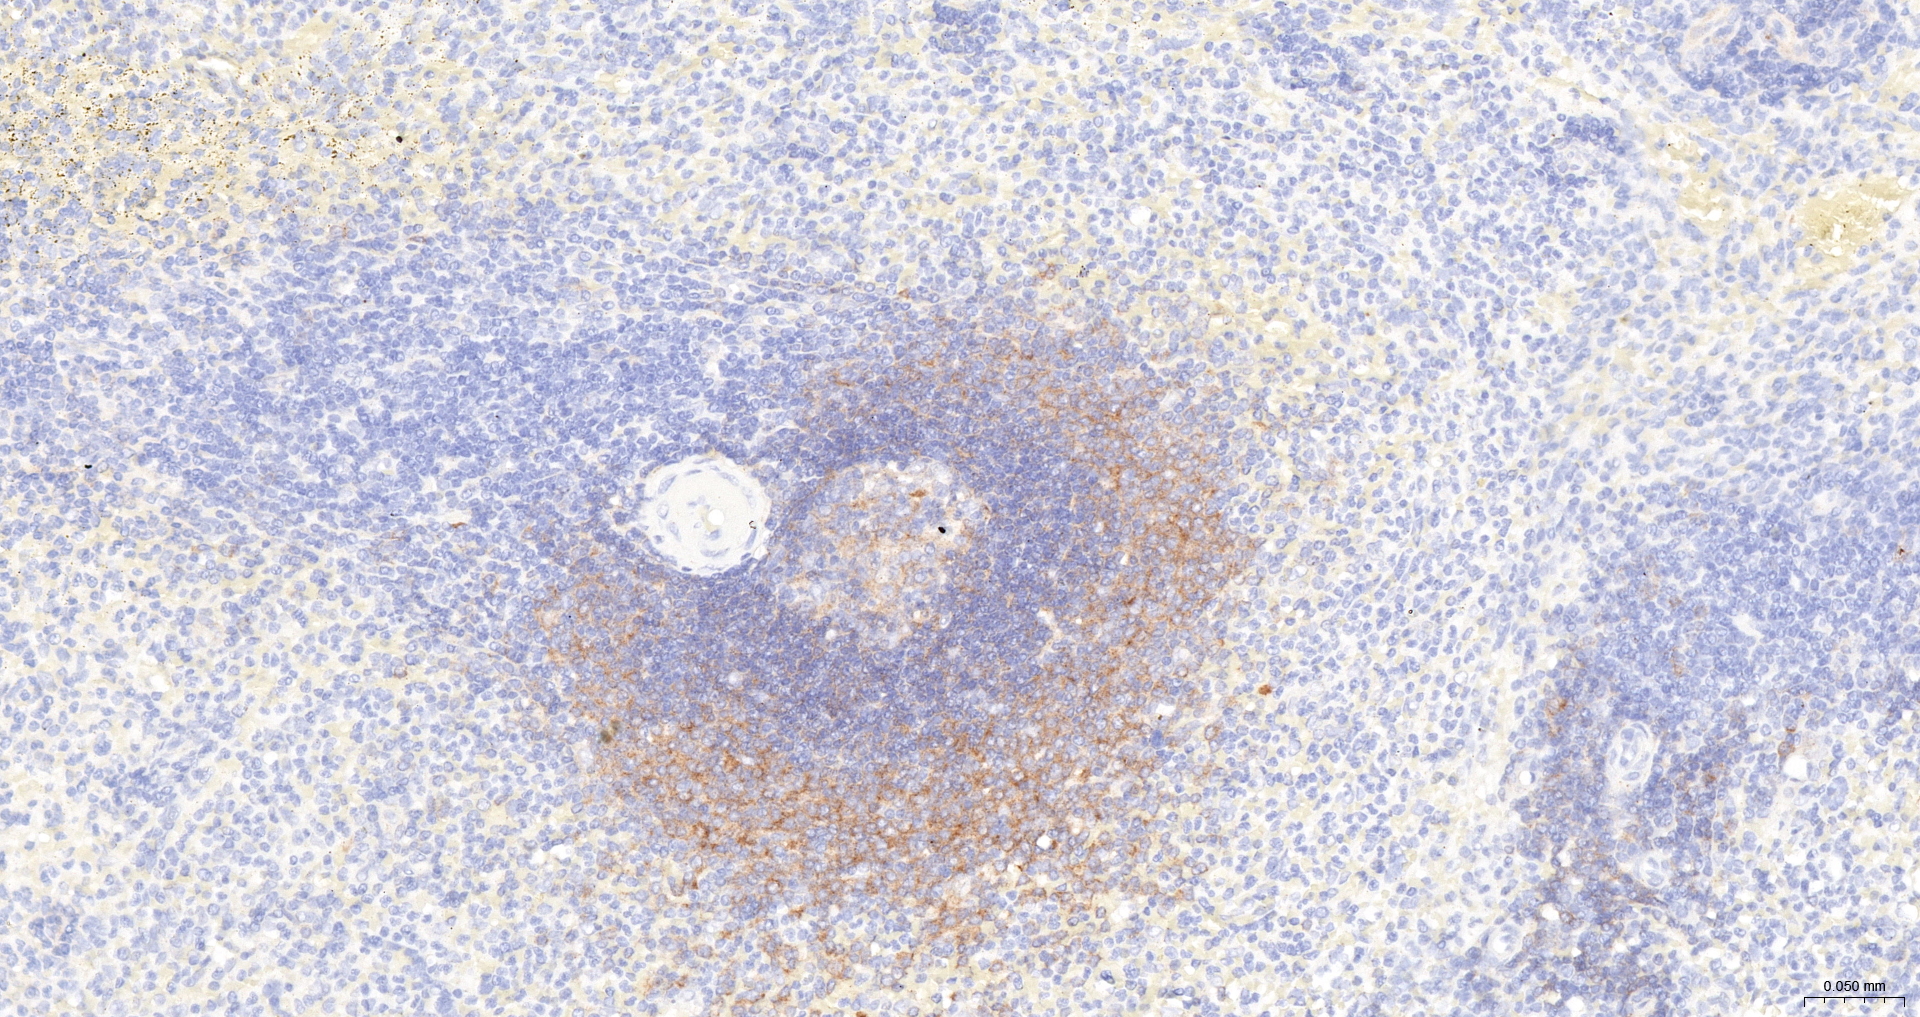

• IHC-P

IHC-P IHC-P1:100-200